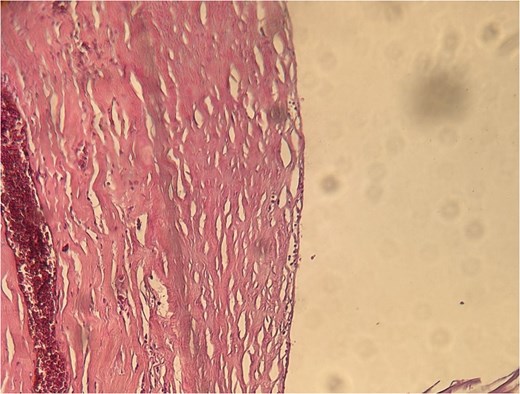

A 60-year-old Moroccan female with no significant medical history presented with chronic periumbilical pain lasting several months, without associated digestive or systemic symptoms, and preserved general condition. Clinical examination revealed periumbilical tenderness. Abdominal ultrasound was unremarkable, prompting an abdominopelvic CT scan, which identified a retroperitoneal inter-aortocaval cystic lesion measuring 86 mm. Surgical exploration revealed a large cystic mass in the mesentery of the small intestine, which was entirely excised. Histopathological examination showed variable-sized cystic cavities with a lymphatic appearance (Fig. 1), lined by flattened and regular endothelium. Some cavities contained pale eosinophilic material interspersed with lymphocytes and areas of red blood cells (Fig. 2). The interstitial tissue exhibited lymphocytic and plasmacytic inflammatory infiltrates. Immunohistochemistry confirmed the lymphatic nature with positivity for Podoplanin/D2–40 (Fig. 3) and CD34 (Fig. 4) and negativity for calretinin (Fig. 5). The patient’s postoperative course was uneventful.

Histopathological examination showing cystic cavities of varying sizes lined by flattened endothelium.